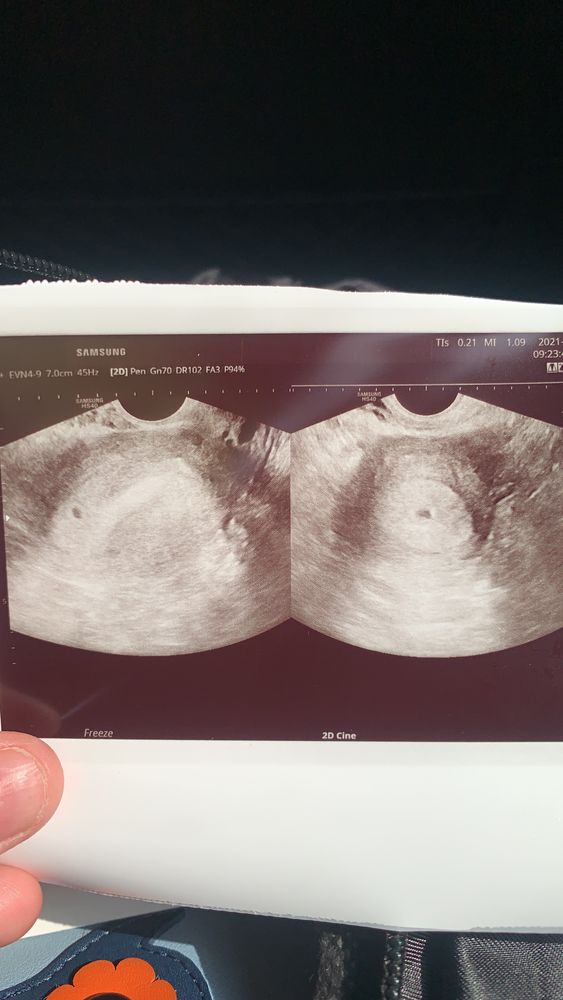

узи на раннем сроке

Изображение

Девочки всем привет.Что думаете насчёт фото. Врач толком ничего не сказал только что придти через неделю на повторное узи посмотреть растет кроха или нет.Тянул немного живот с 21-23.06 но потом пе